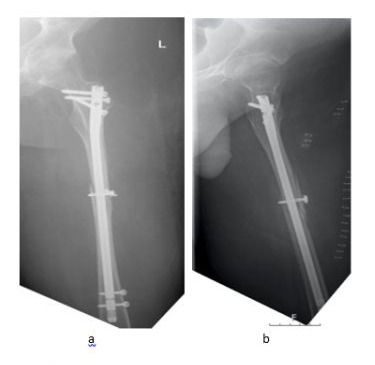

Ten days after surgery the patient resumed his studies at university. Due to the Corona pandemic all courses were held online. Nevertheless, he was able to sit in his wheelchair for at least 8 hours a day. After 12 weeks the fracture had healed (Figure 3a-d). The patient could be mobilized into a standing position.

Figure 3a-d: Follow-up composed X-rays after 12 weeks. All cortices are bound by callus formation in a.p. (Figure. 3a,b) and lateral (Figure. 3c,d) views.

Proximal humerus nails have previously been used in pediatric and adolescent patients for the treatment of femoral pathologies [6,11]. Gordon et al. described femoral lengthening in nine children over a humeral intramedullary nail. The authors witnessed two operative fractures and one fracture after removal of the distal locking pin. Furthermore, two infections occurred. The infections were all due to the half-pins used for femoral lengthening and not to the humeral nail. One operative fracture was due to the half pins, another occurred after removal of the distal locking screw. One fracture developed through the distal locking site resulting in loss of reduction and nail replacement [11]. In a further paper of the same group, 15 children with femoral shaft fractures were treated by humeral nails [6]. No complications were found in these patients. Since our patient suffered from a femoral fracture, we were confident, that a rigid humeral nail might be a safe procedure. The additional cable cerclage was performed to restore the medullary canal before the nailing procedure was started. The callus bridge, which is clearly visible at 3 months, proves the vitality of the periosteum of the wedge fragment at the fracture site.